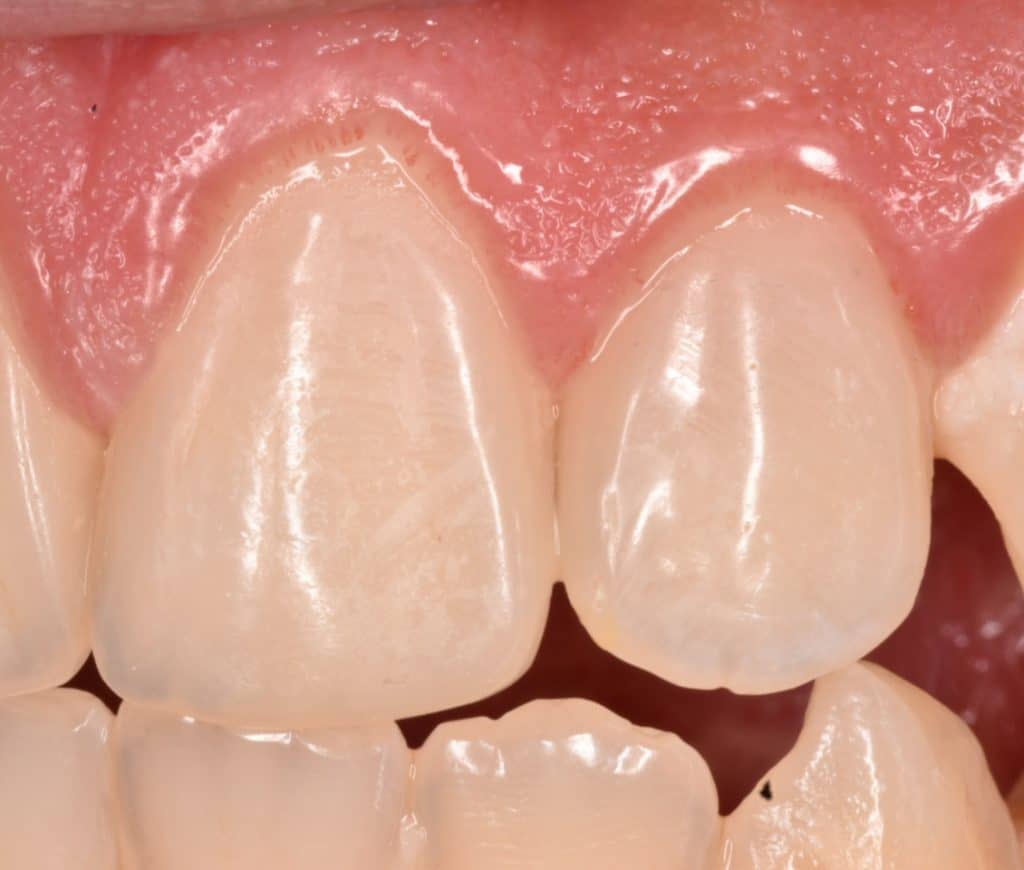

Initial situation showing large cervical caries in all his anterior teeth , I will take these 2 teeth as example the other teeth will posted in another post